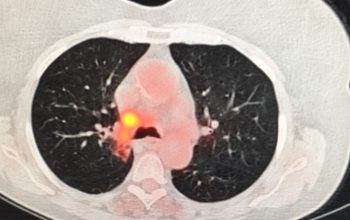

Παραδείγματα πότε μπορεί να βοηθήσει η εξέταση (ΕBUS) στη διάγνωση